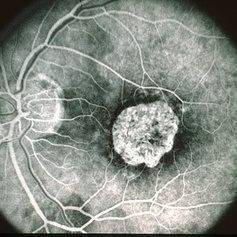

Age Related Macular Degeneration - Geographic Atrophy

Geographic Atrophy.

Imaging device: Retina Diseases Imaging Reading Center

Condition/keywords: advanced geographic atrophy, atrophic scar, atrophic spot, geographic atrophy, macula lesion, pigment epithelial atrophy, red-free, window defect